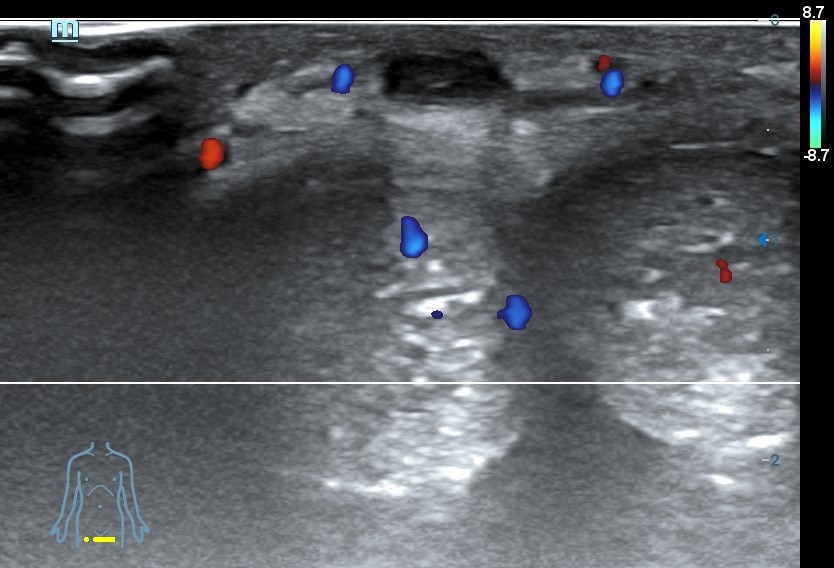

Ecografía clínica pene: se visualiza vena dorsal rellena de material hipoecogénico heterogéneo, no compresible, no flujo con Doppler color.

Diagnóstico: Trombosis vena dorsal del pene.